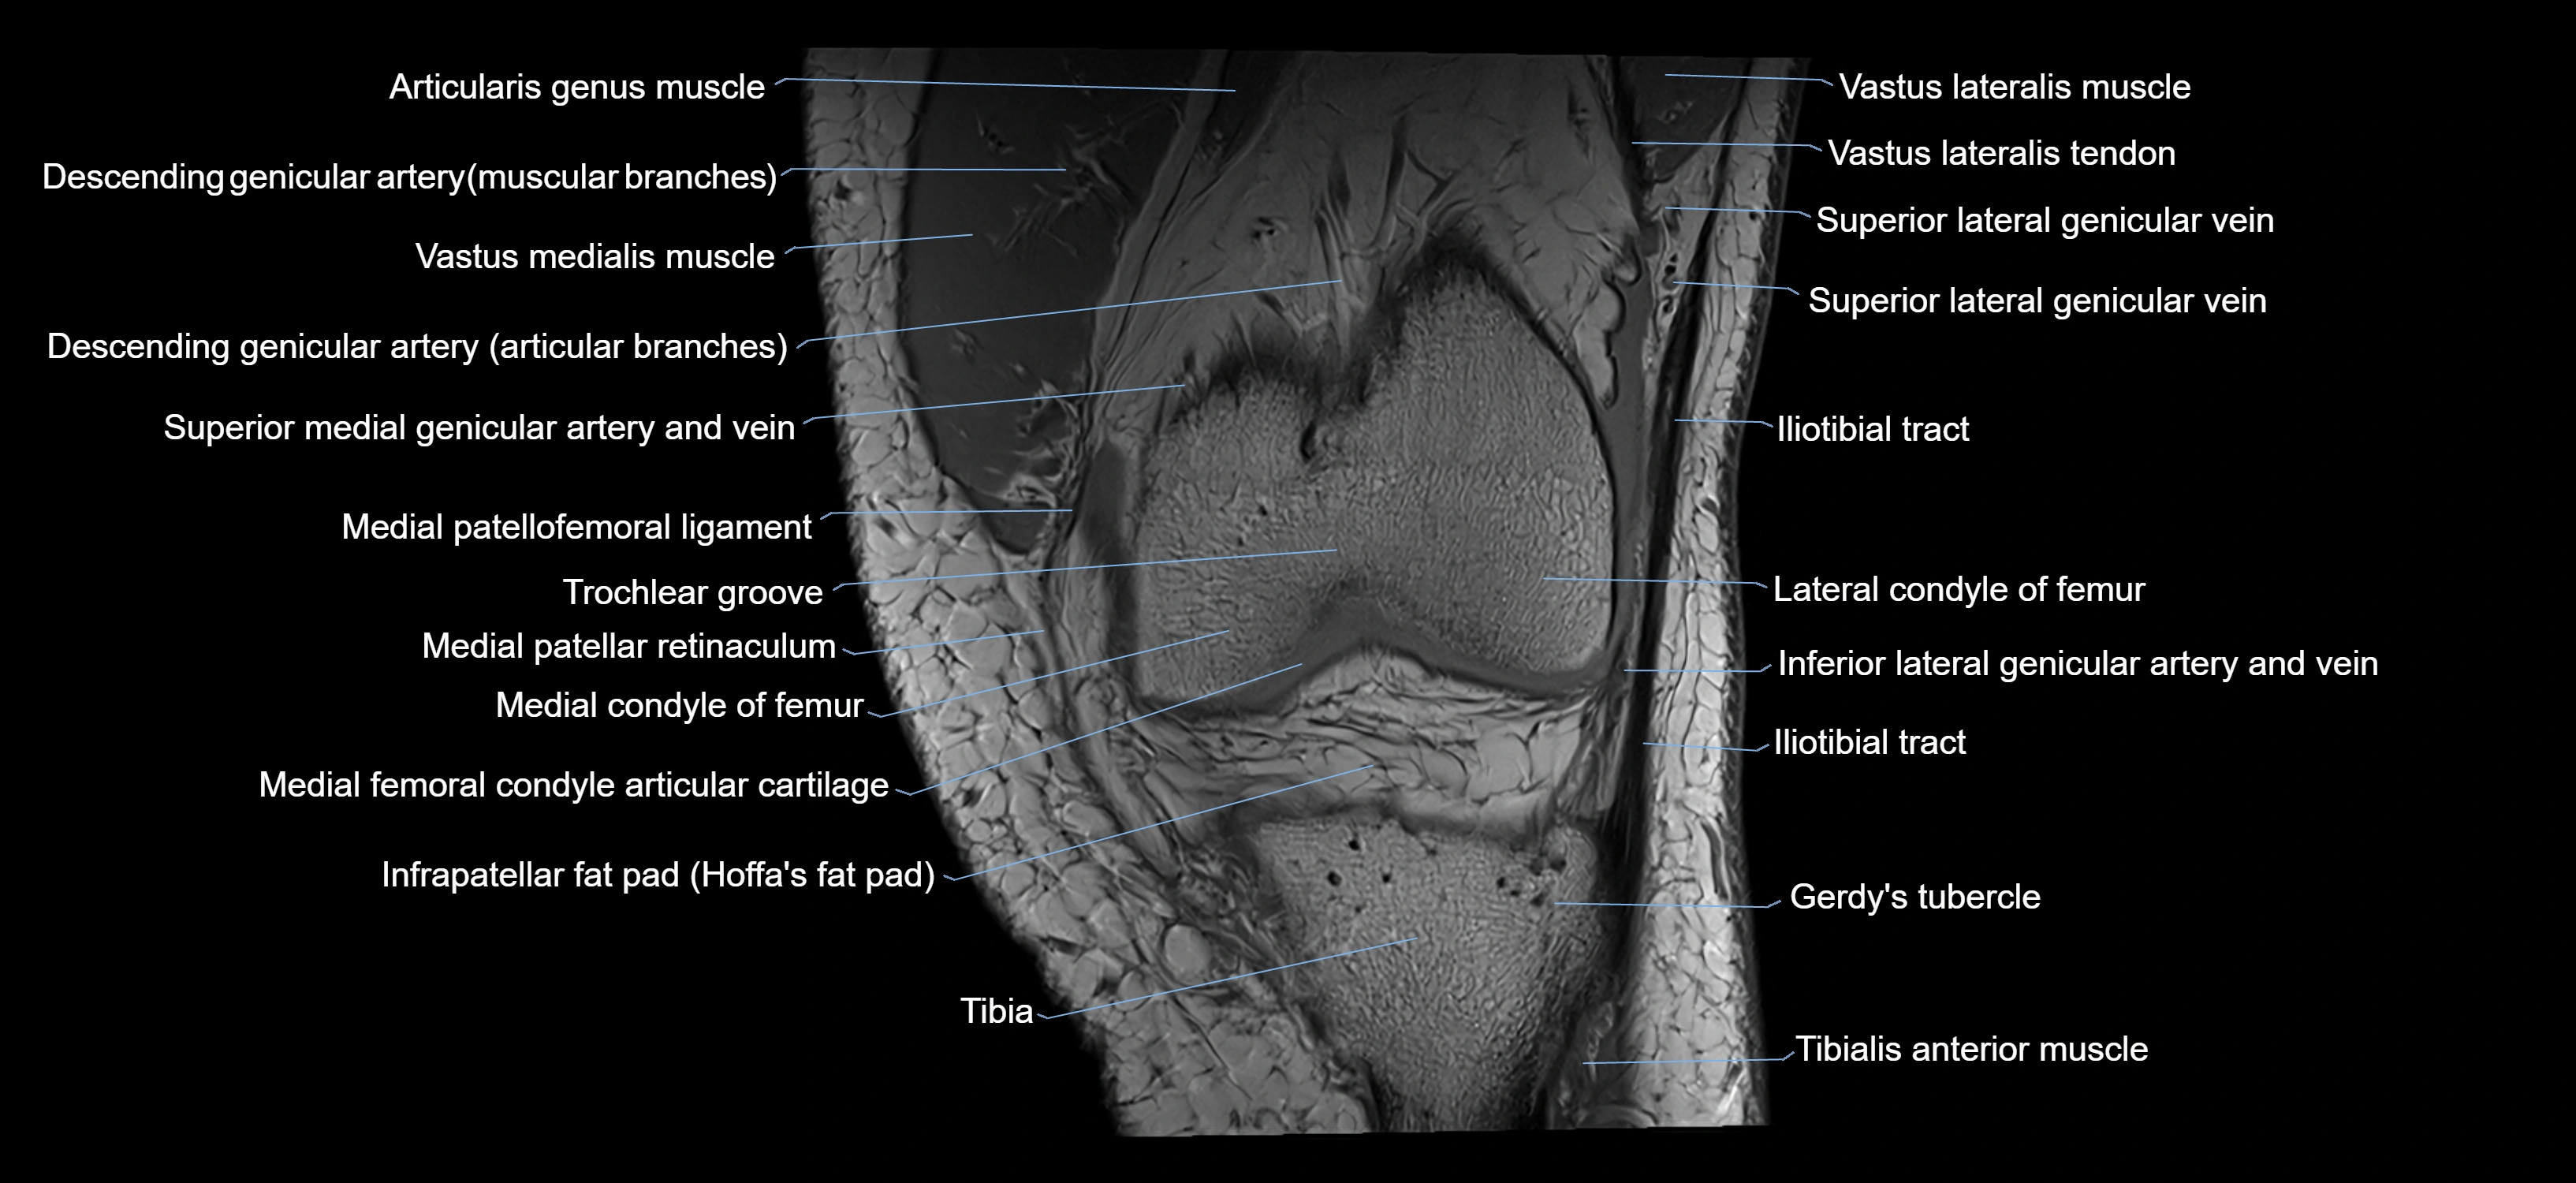

- Descending genicular artery (Articular branches)

- Gerdy’s tubercle

- Infrapatellar fat pad

- Lateral condyle of femur

- Lateral patellofemoral ligament

- Medial condyle of femur

- Medial patellar retinaculum

- Medial patellofemoral ligament

- Patellar tendon (patellar ligament)

- Prefemoral fat pad

- Superior lateral genicular artery

- Superior lateral genicular vein

- Superior medial genicular artery

- Superior medial genicular vein

- Tibia

- Tibialis anterior muscle

- Trochlear groove

- Vastus Lateralis Obliquus Muscle

- Vastus lateralis muscle

- Vastus medialis muscle